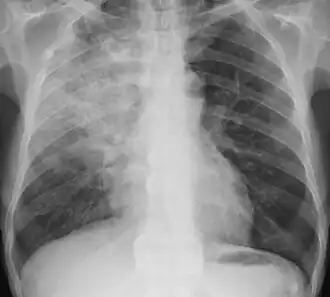

Radiography is the most common form of imaging used in the initial assessment of a foreign body presentation. Most patients receive a chest x-ray to determine the location of the foreign body.[2] Lateral neck, chest, and bilateral decubitus end-expiratory chest x-rays should be obtained in patients suspected of having aspirated a foreign body.[6] However, the presence of normal findings on chest radiography should not rule out foreign body aspiration as not all objects can be visualized.[2] In fact, up to 50% of cases can have normal findings on radiography.[7] This is because visibility of an object depends on many factors, such as the object's material, size, anatomic location and surrounding structures, as well as the patient's body habitus.[13] X-ray beams only show an object if that object's composition blocks the rays from traveling through, making it radiopaque and appearing lighter or white on the image. This also requires it to not be stuck behind something that blocks the beams first.[13] Objects that are radiopaque include items made of most metals except aluminum, bones except most fish bones, and glass. If the material does not block the x-ray beams it is considered radiolucent and will appear dark which prevents visualization.[13] This includes material such as most plastics, most fish bones, wood, and most aluminum objects.[13]

Signs on x-ray that are more commonly seen than the object itself and can be indicative of foreign body aspiration include visualization of the foreign body or hyperinflation of the affected lung.[13] Other x-ray findings that can be seen with foreign body aspiration include obstructive emphysema, atelectasis, and consolidation.[8]